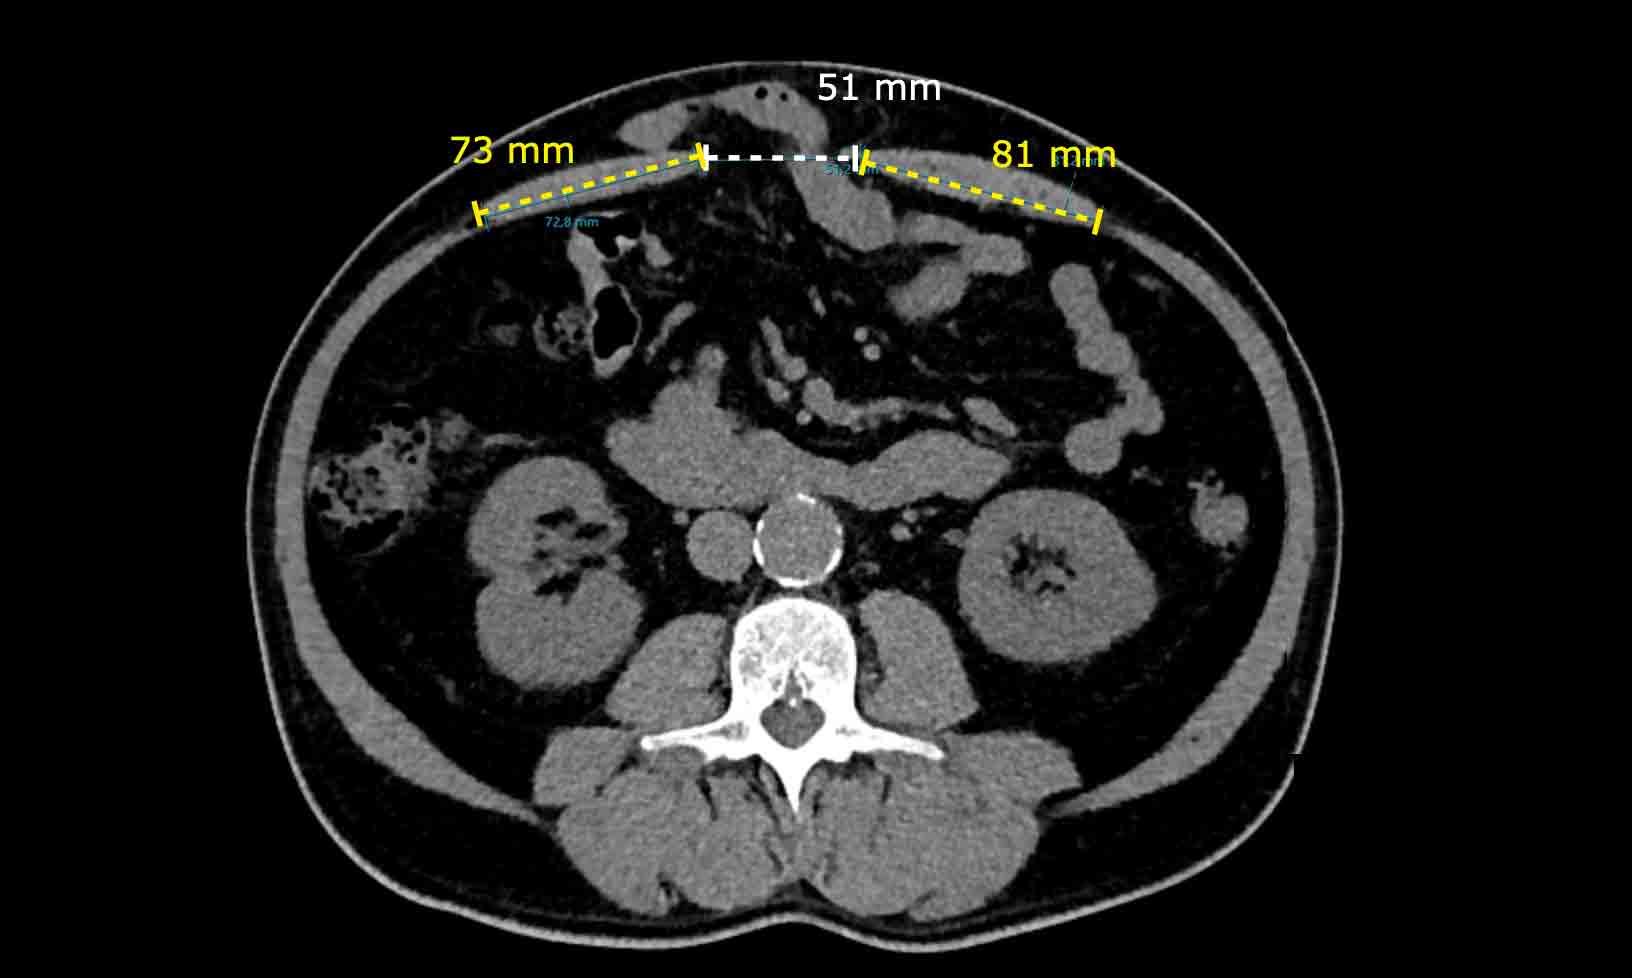

Hình ảnh

Ở một bệnh nhân khác, Tỷ lệ Cơ thẳng bụng trên Khuyết tật là: (73 mm + 81 mm) / 51 mm = 3.

Trái ngược với trường hợp trước, việc đóng thoát vị có thể thực hiện được mà không cần tiến hành kỹ thuật tách thành phần.